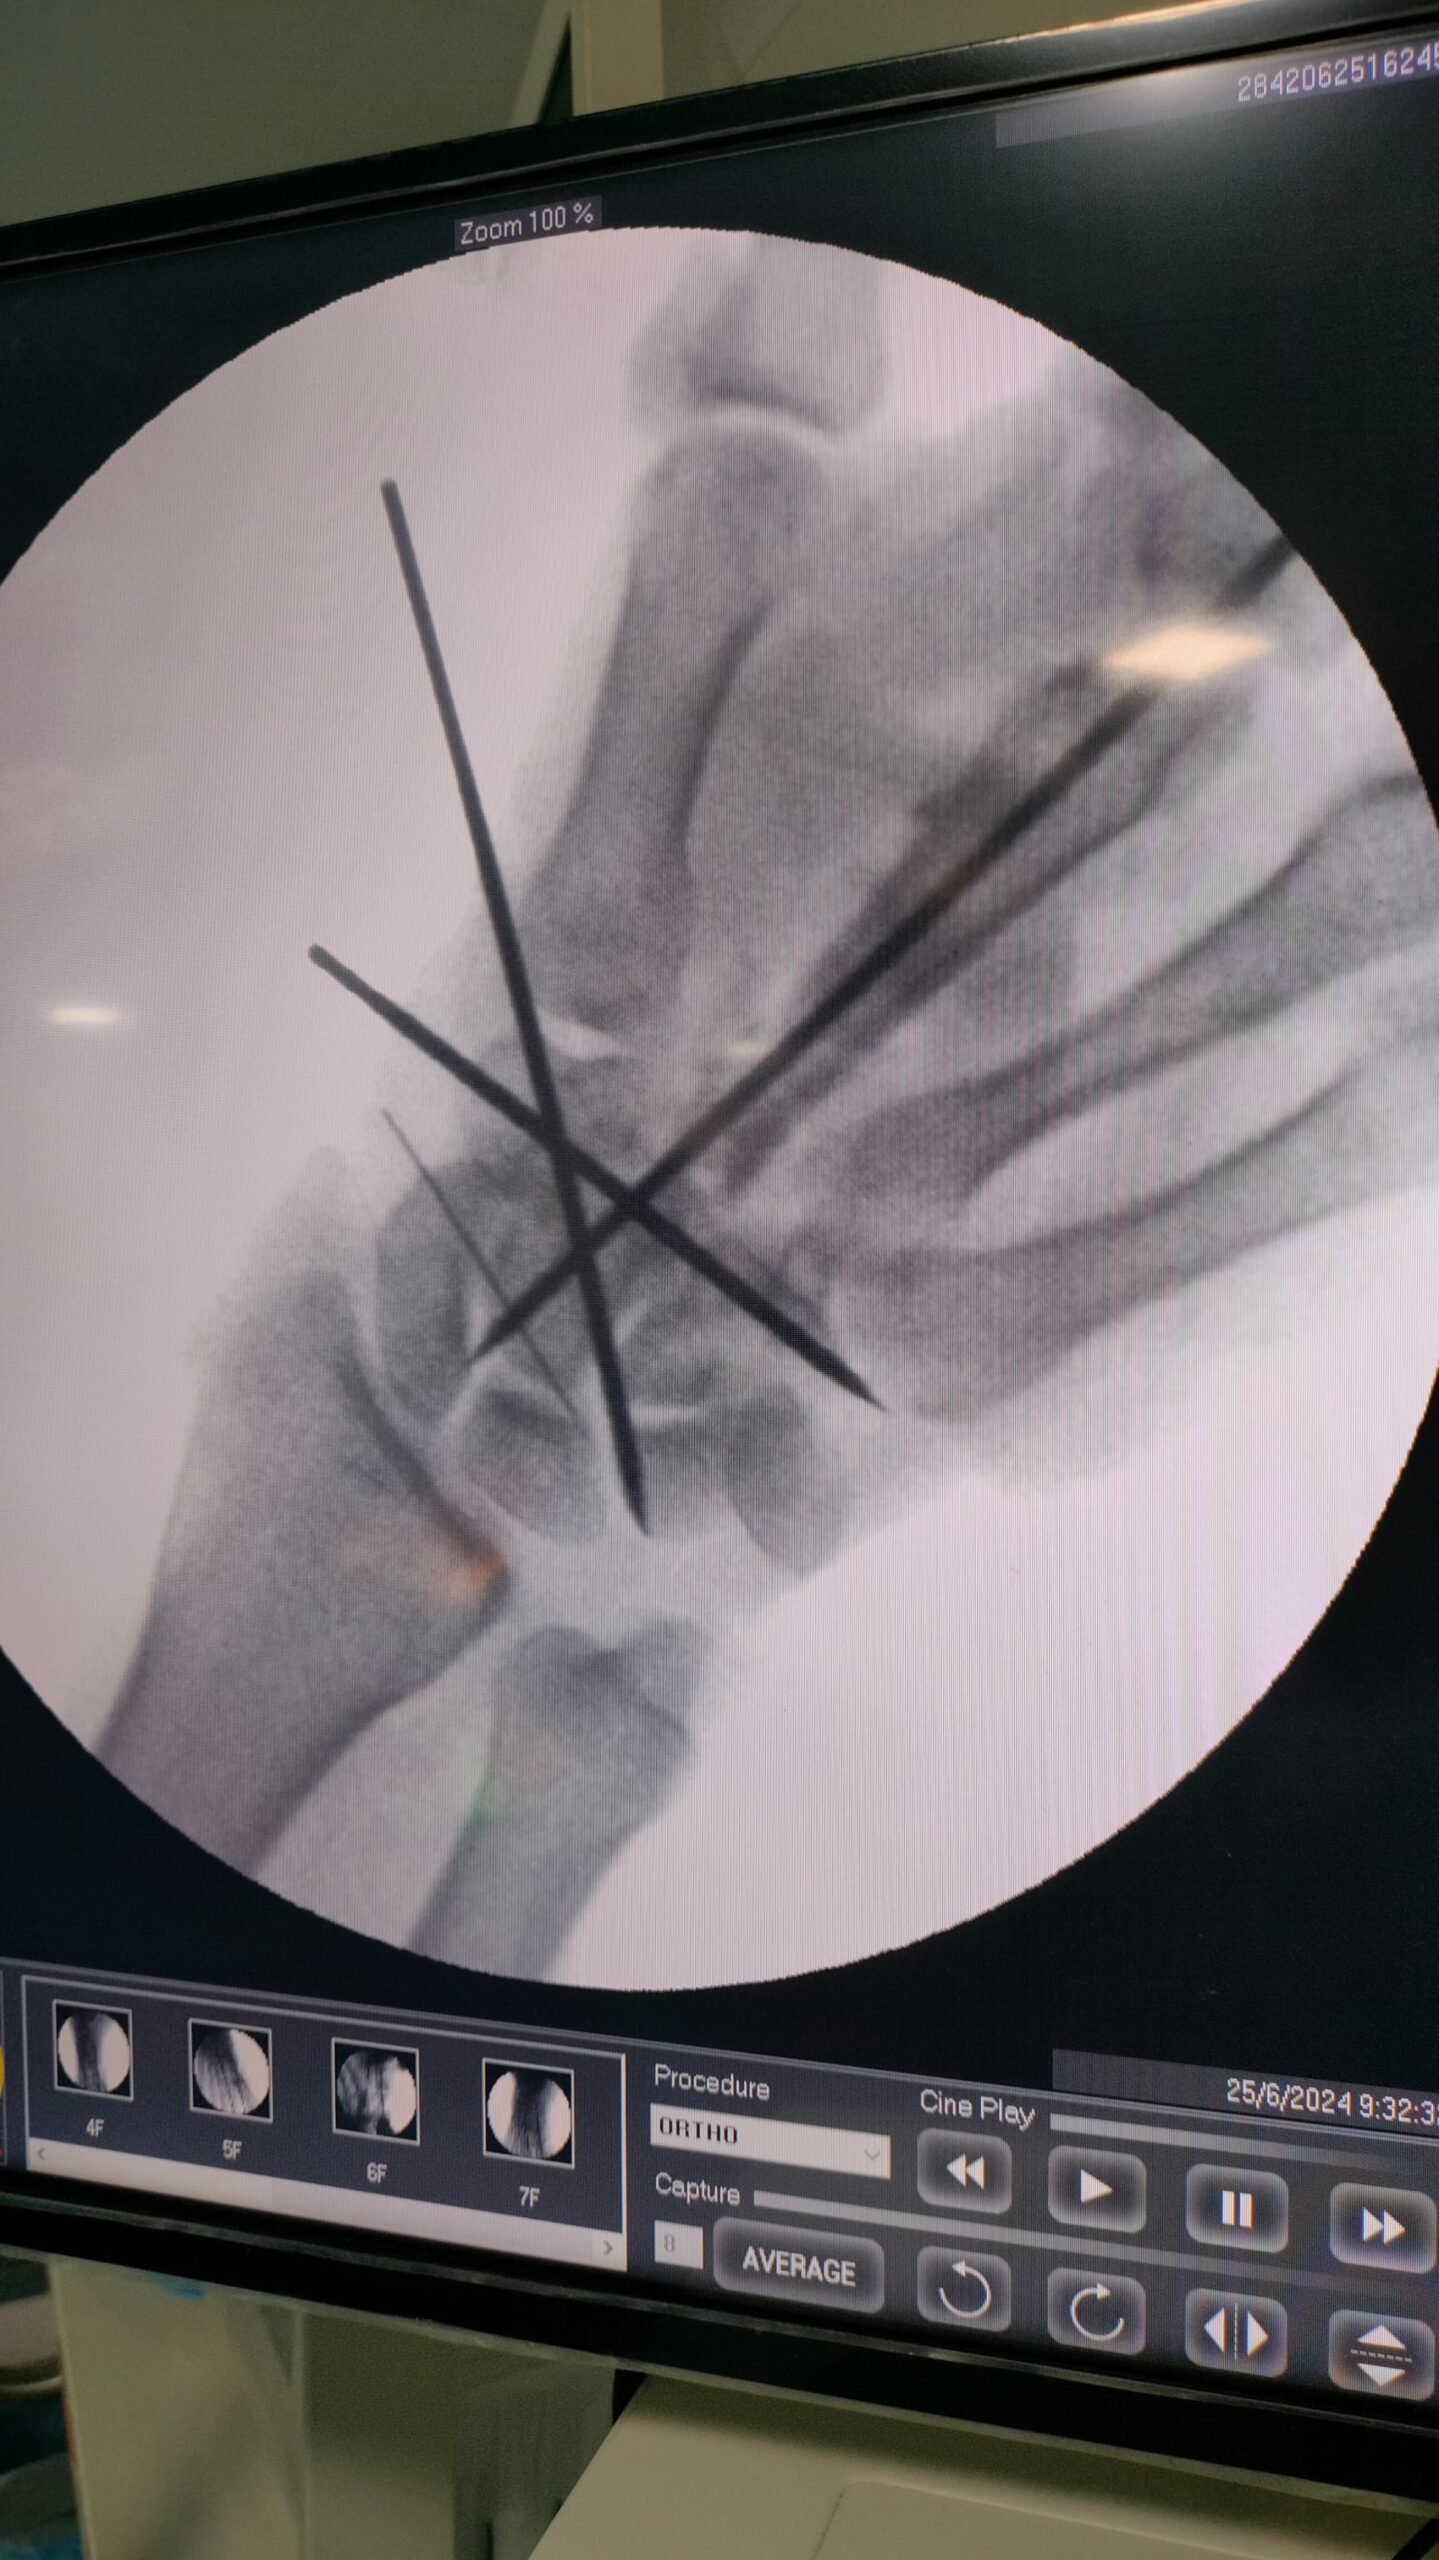

Fracture and Trauma Surgery

Gallery